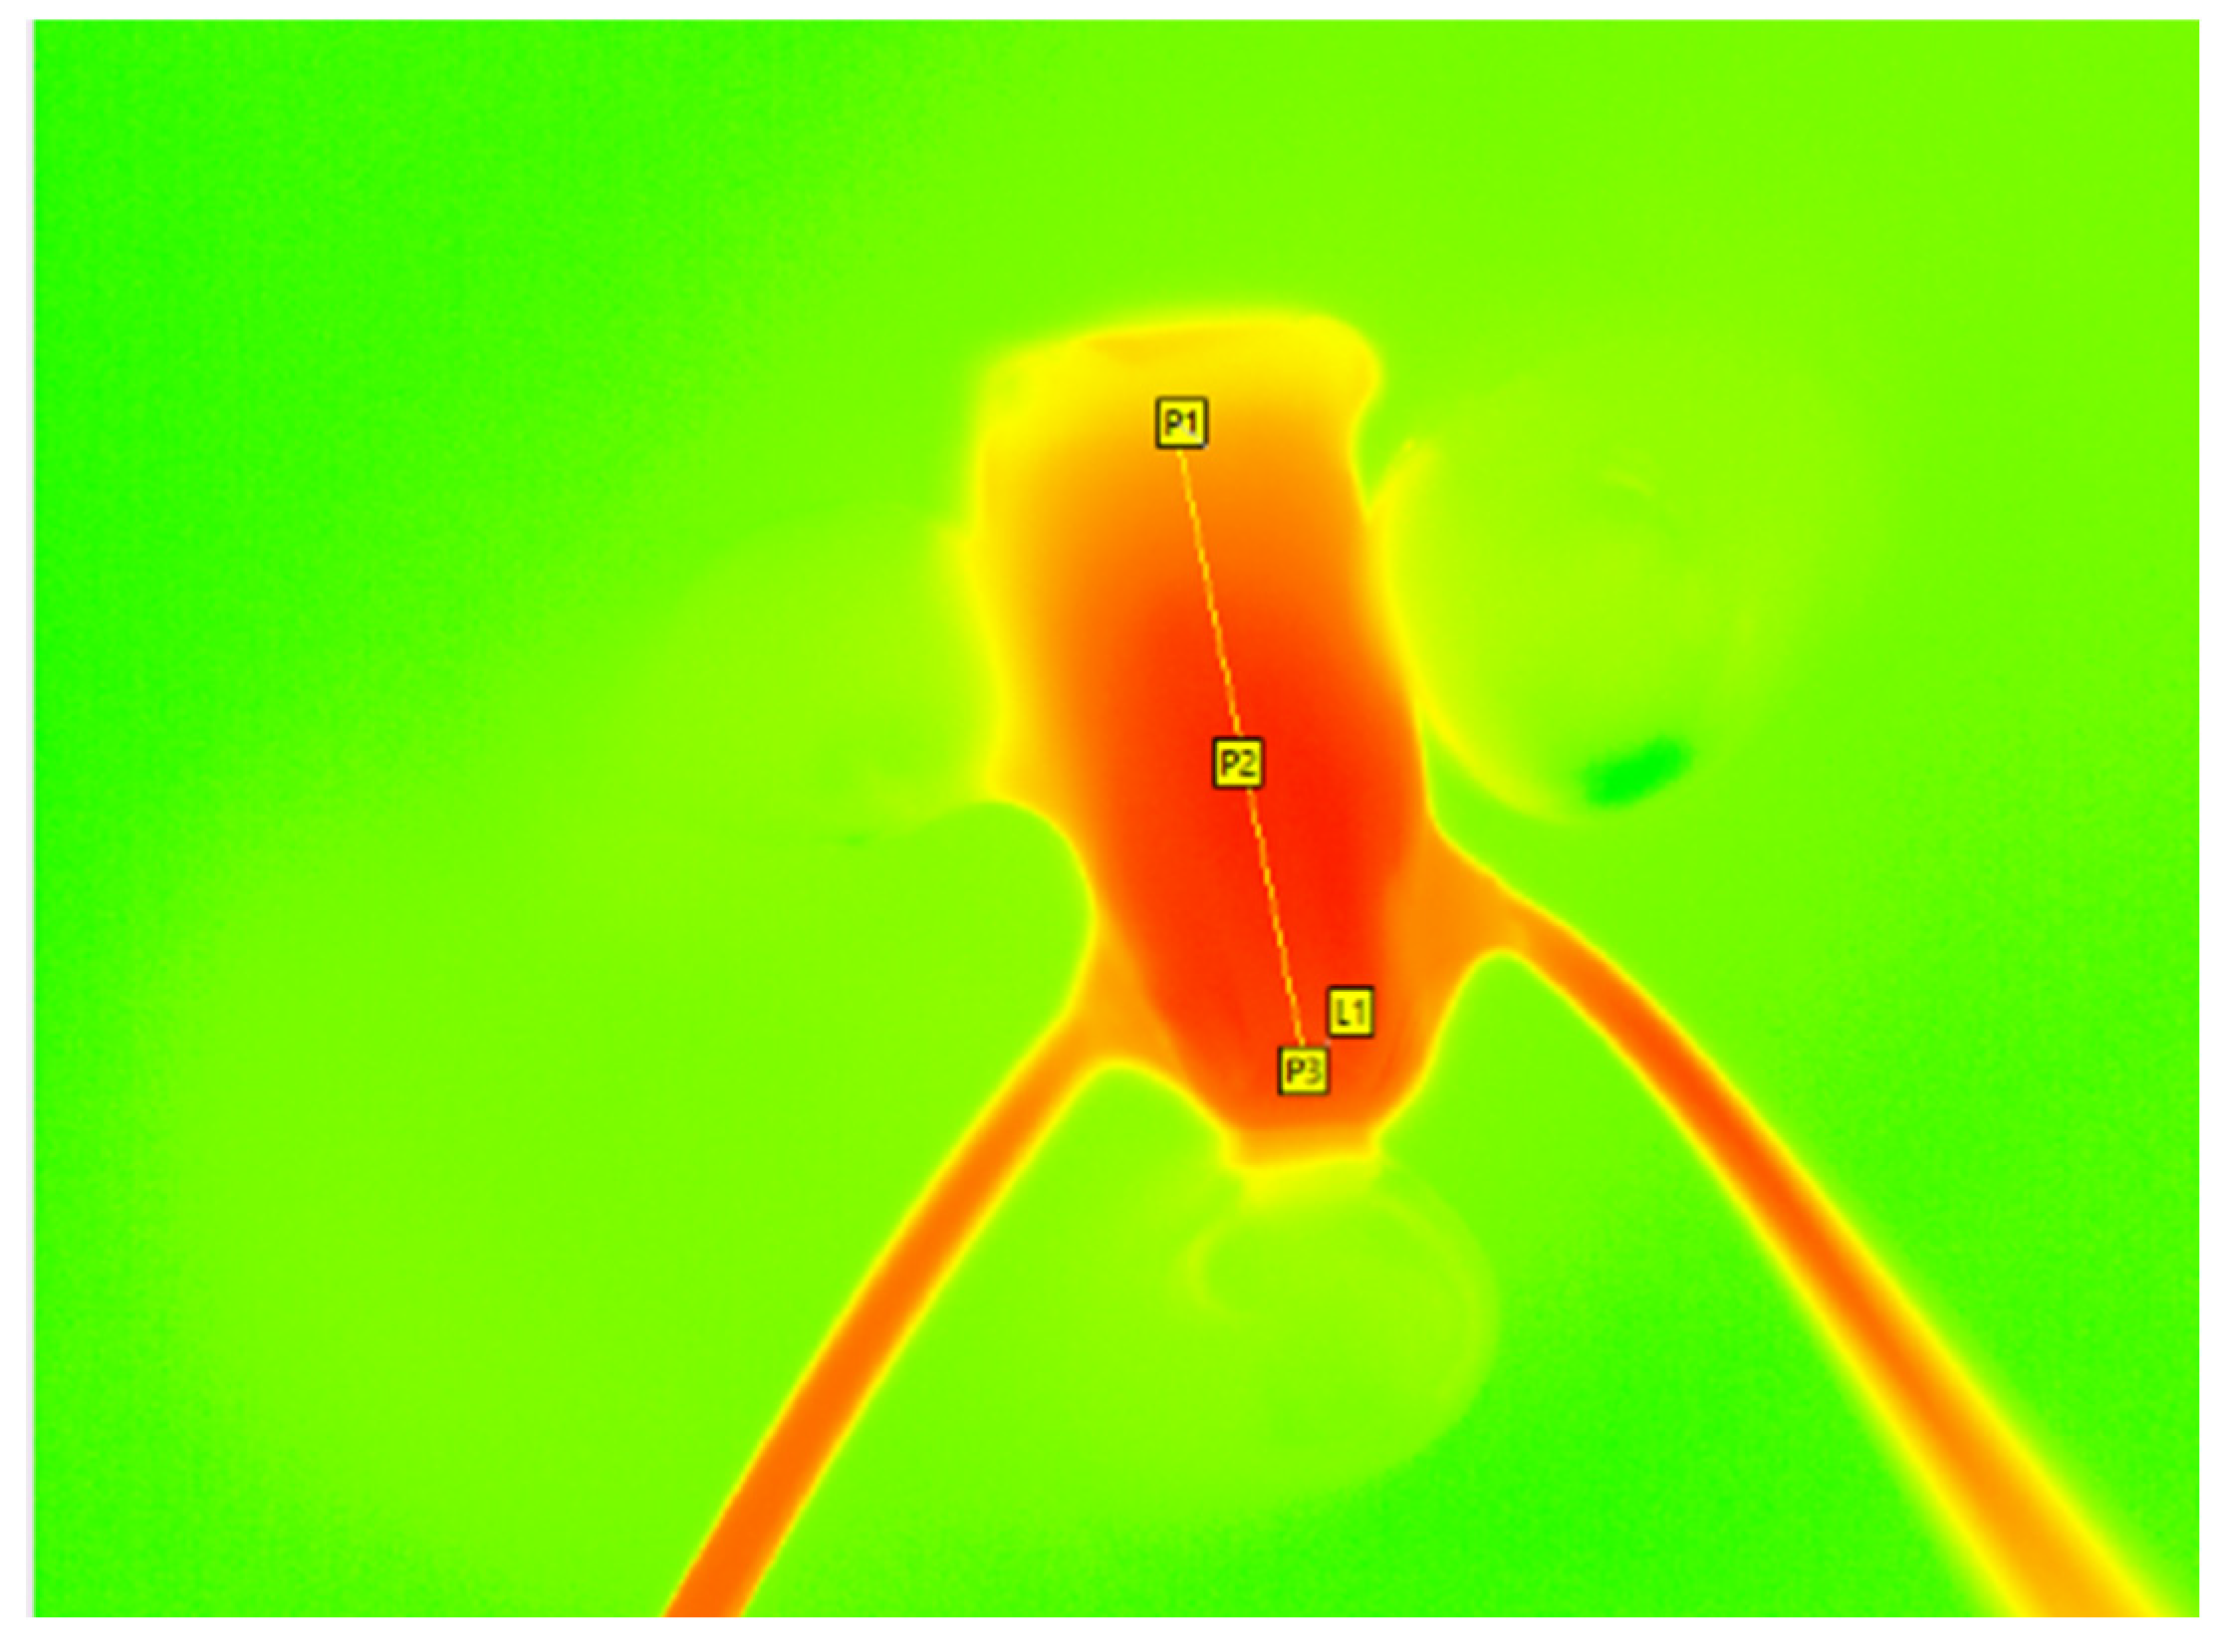

A temperature–time diagram was created using the IRBIS 3.1 plus software (InfraTec GmbH Infrarotsensorik und Messtechnik, Dresden, Germany), and the data was displayed in an Excel sheet (Microsoft Office Professional Plus 2016, Microsoft, Redmond, DC, USA). The data provided the initial temperature (T0), the maximum temperature (Tmax), the latency time until the maximum temperature is reached, and the delta between Tmax and T0. The data was not normally distributed. The values were analyzed statistically using the Kruskal–Wallis test. If there was a significant difference between the groups (p < 0.05), the Mann–Whitney pairwise test using the sequential Bonferroni procedure was performed. p-values < 0.05 was considered statistically significant. For the statistical analysis, three measuring points (P1, P2, and P3) were set individually in the tooth samples, located in the coronal, middle, and apical parts of each sample. To measure the mean temperature, the points were connected using a line (L1, Figure 2). To illustrate the results, box plot diagrams were created to demonstrate the median, first and third quartiles, and the minimum and maximum values. Outliers were defined as values exceeding 1.5 to three times the interquartile range. These are marked as dots, whereas distant outliers are marked as asterisks.

Figure 2. Temperature measurement using a thermal imaging camera (VarioCAM HD; InfraTec GmbH Infrarotsensorik und Messtechnik, Dresden, Germany) during obturation. The P1, P2, and P3 points are set at the coronal, middle, and apical thirds, with the line L1 connecting them.